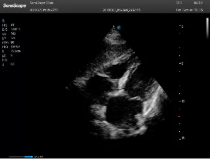

不同的探頭對應(yīng)于不同的臨床領(lǐng)域,不同的探頭頻率也應(yīng)用于不同的人體組織。超聲波在人體中的衰減與探頭頻率有關(guān),探頭頻率越高,穿透力越弱,分辨率越高,而探頭頻率越低,穿透力越強,分辨率越低。因此在檢查淺表器官時應(yīng)選用高頻探頭,而檢查深部臟器時則選用穿透性強的低頻探頭。